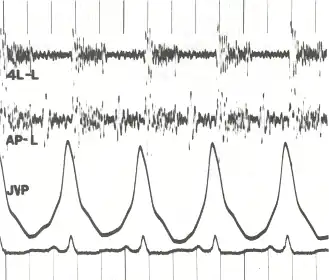

Phonocardiogram and jugular venous pulse tracing from a middle-aged man with pulmonary hypertension caused by cardiomyopathy. The jugular venous pulse tracing demonstrates a prominent a wave without a c or v wave being observed. The phonocardiograms (fourth left interspace and cardiac apex) show a murmur of tricuspid insufficiency and ventricular and atrial gallops.